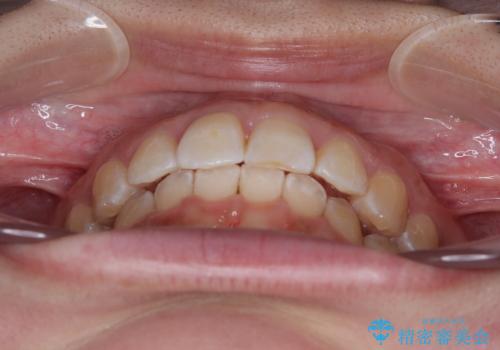

前歯のデコボコをインビザライン矯正で綺麗に改善

- 上下前歯のデコボコを気にして来院された患者様です。

全体的に叢生は軽度であったため、インビザラインにて矯正治療を行うこととしました。

舌の突出癖改善がうまくいかず、途中で舌小帯の切除を行いました。

気になる段差を納得いくまで改善させたため、治療期間は長くなりましたが、綺麗な仕上がりとなりました。